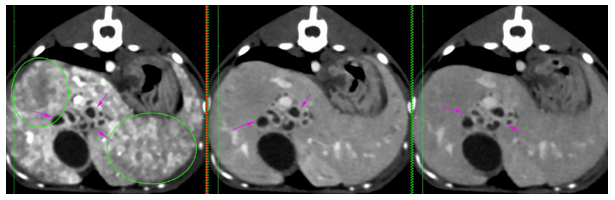

At the age of 4 months, a dual-phase (portal and delayed-venous) abdominal CT was performed to further describe the lesions and the extent of the process (SOMATON Scope CT VC40, 16-slice CT, Siemens, USA). A non-ionic iodinated contrast agent consisting of iohexol (Omnipaque™, GE Healthcare) was administered via an intravenous bolus. Post-contrast results of the examination were represented by hepatomegaly with large tubular structures, non-enhancing and hypoattenuating to the surrounding parenchyma, present throughout the liver (Figure 4A, C-red arrowhead). The tubular structures follow the approximate location of the biliary ducts with a branching pattern within the liver, close to the hepatic vasculature. (Figure 4A, B-orange arrowhead). There was difficulty encountered in identifying the gallbladder, as a result of numerous distended loops (Figure 1A-yellow arrows). A 9 mm, large, distended structure extending throughout the right limb of the pancreas to the region of the duodenal papilla was noted (Figure 4D-green arrows). The pancreatic duct was mildly distended, measuring less than 3 mm in diameter. The distended structures were filled with fluid attenuation content (10 – 20 HU) with a variably thickened wall (less than 4 mm). The hepatic changes had a marked mass effect, with right-sided displacement of the caudal vena cava noted due to the mass effect of hepatic changes. The mesenteric vasculature was relatively prominent, with many tortuous vessels present medial at the left kidney in the region of the left gastric vein and cranial mesenteric artery (Figure 4D-purple arrows). There was no evidence of a single well-defined congenital extrahepatic or intrahepatic shunt.

Figure 4 Transverse (A, B, D) and coronal (C) abdominal CT 0.75 mm slice image- Distended intrahepatic ducts causing a mass effect at the level of the cranial abdomen (red arrow) and pancreatic cyst (green arrow). A mild peritoneal effusion was noted, although this finding was unremarkable for the age of the patient.